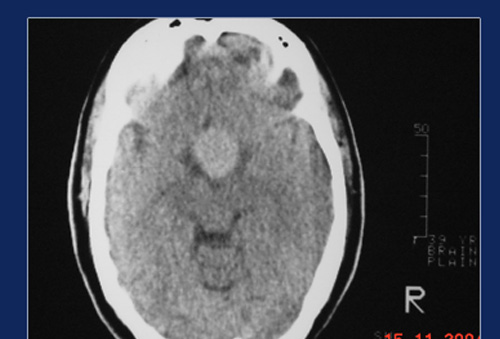

The pituitary gland is a tiny body about the size of a peanut situated at the center of the skull with its stalk attached to the base of the brain. It produces a number of hormones, which control other endocrine glands. Sometimes a tumor of this gland can result in hormonal imbalance with growth and other metabolic derangements. The neurosurgical approach to this gland is fraught with difficulties owing to its location and vision shadow areas, and also injury to cranial nerves and other parts of the brain.

This gland can be very easily approached through the nose under Endoscopic control, since it is just a thin plate of bone away from the sphenoid sinus. Sphenoid sinus is routinely opened during Endoscopic nasal surgery to open the pituitary fosse through this sinus. Complete removal of tumor is possible since there are no vision shadow areas in this approach.